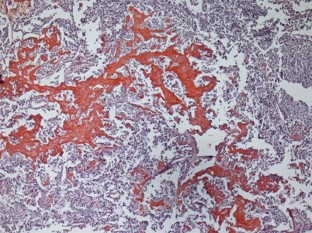

Abb. 1

Abb. 2

Abb. 3

Abb. 4

Abb. 5